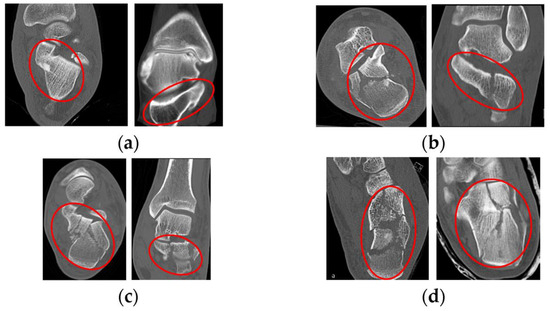

- Rahmaniar, W.; Wang, W.-J. Real-Time Automated Segmentation and Classification of Calcaneal Fractures in CT Images. Appl. Sci. 2019, 9, 3011. [Google Scholar] [CrossRef]

- Song, Q.; Li, T.; Xia, H.; Li, Y.; Feng, C.; Lin, Y.; Wang, H.; Hu, J.; Jiang, Q. Three-Dimensional Printed Cast Assisted Screw Fixation of Calcaneal Fractures: A Prospective Study. BMC Musculoskelet. Disord. 2023, 24, 802. [Google Scholar] [CrossRef]